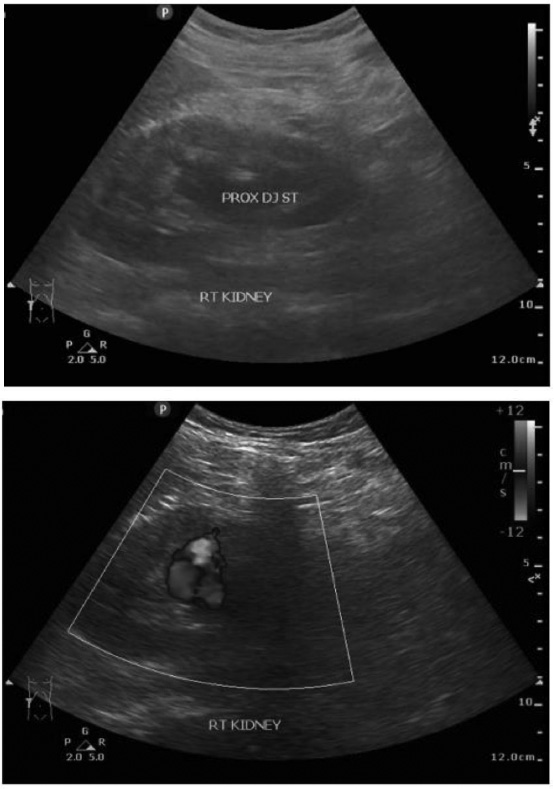

Three weeks post-procedure, the patient returned with severe hematuria and anemia. The physical evaluation during hospitalization revealed no abnormalities in the lung, cardiac, or limb examinations and the vital signs. The laboratory result of the erythrocyte was 2.75 × 10^6/uL, with the leukocyte value recorded at 7.4 × 10^3/uL and hemoglobin measured at 7.5 g/dL, urea levels at 12.0 mg/dL, and serum creatinine concentration at 1.6 mg/dL. The outcomes of all subsequent tests exhibited normal findings, including bleeding time, blood coagulation time, and plasma electrolytes. We assessed the patient for recurrent hematuria and a suspected pseudoaneurysm in the right renal artery. The patient underwent an ultrasound examination, which showed two-way flow with a “yin-yang sign” that could be a pseudoaneurysm in the right kidney and moderate hydronephrosis in the right kidney with a DJ stent in situ (Fig. 3). Due to recurrent hematuria, we conducted a second angiography and embolization again without prior CT angiography.

Ultrasound image post embolization with recurrent hematuria.